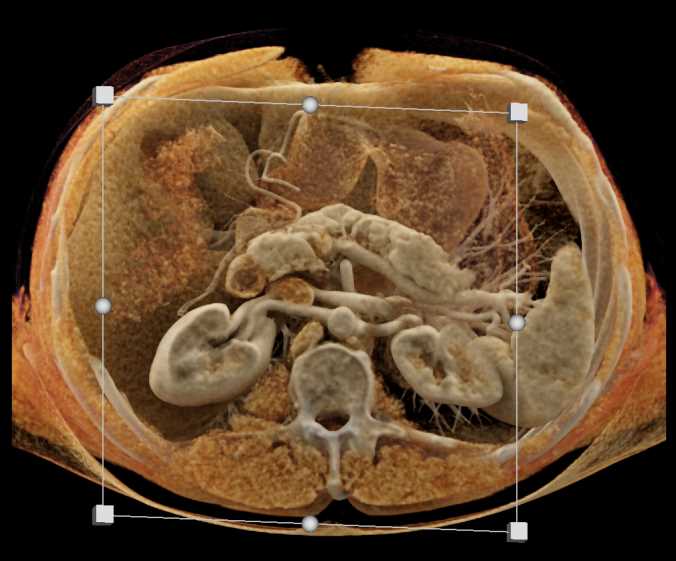

Subtle Neuroendocrine Tumor Body of Pancreas